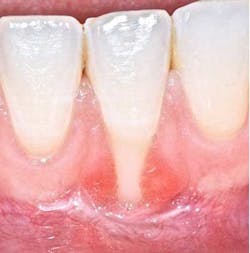

According to the proceedings from the 2014 American Academy of Periodontology Regeneration Workshop, root coverage may be attained through the application of a variety of surgical procedures. These outcomes are generally measured by reduced defect depth, gain in clinical attachment, and an increase in keratinized tissue. The associated systematic reviewprovides clear evidence that a subepithelial connective tissue graft (SCTG) procedure offers the best outcome for mean and complete root coverage, as well as an increase in keratinized tissue. (4,5) Strong evidence also supports biomaterials such as acelullar dermal matrix grafts (ADMG) or enamel matrix derivative (EMD) in conjunction with a coronally advanced flap (CAF) that can be used as an alternative to treat Miller Class I and II single-tooth gingival recession defects (figures 1 and 2). (6)Another suggestion from the proceedings was that using a split-thickness flap or tunnel technique can help to revascularize the graft by maintaining an excellent vascular supply to the flap.

Depending on the severity and extent that the mucogingival defects present, we often administer a hybrid/combination therapy. Many of our patients previously experienced mucogingival grafting procedures at other offices, searched the Internet, or discussed with friends who have had soft-tissue grafts, and as a result they are extremely fearful of the dreadful “pizza burn” that one may experience after harvesting from the palate. As reported in the literature and confirmed clinically in our office, with the addition of an enamel matrix protein, patients consistently report minimal postoperative swelling and discomfort. This has been a huge game changer for our practice and will be for yours too (figure 3). (7)